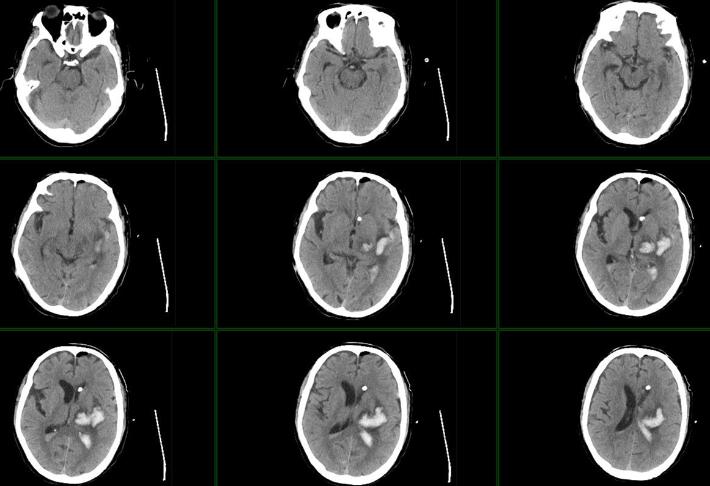

术后第一日,患者神志较前好转,GCS评分10分,神志昏睡。复查颅脑CT:左侧脑室血肿较前明显减少,三脑室、四脑室血肿密度减低。

术后持续脑室外引流1周,未行尿激酶注入,复查颅脑CT:左侧脑室血肿较前明显减少,三脑室、四脑室血肿消失。脑内血肿吸收期改变。